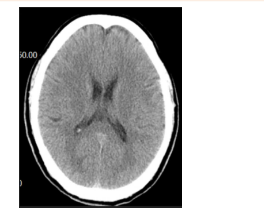

急诊心电图:未见明显异常。头颅CT:如图。

CT

(3)头颅CT未见明显异常,可排除脑出血。(0.5分)